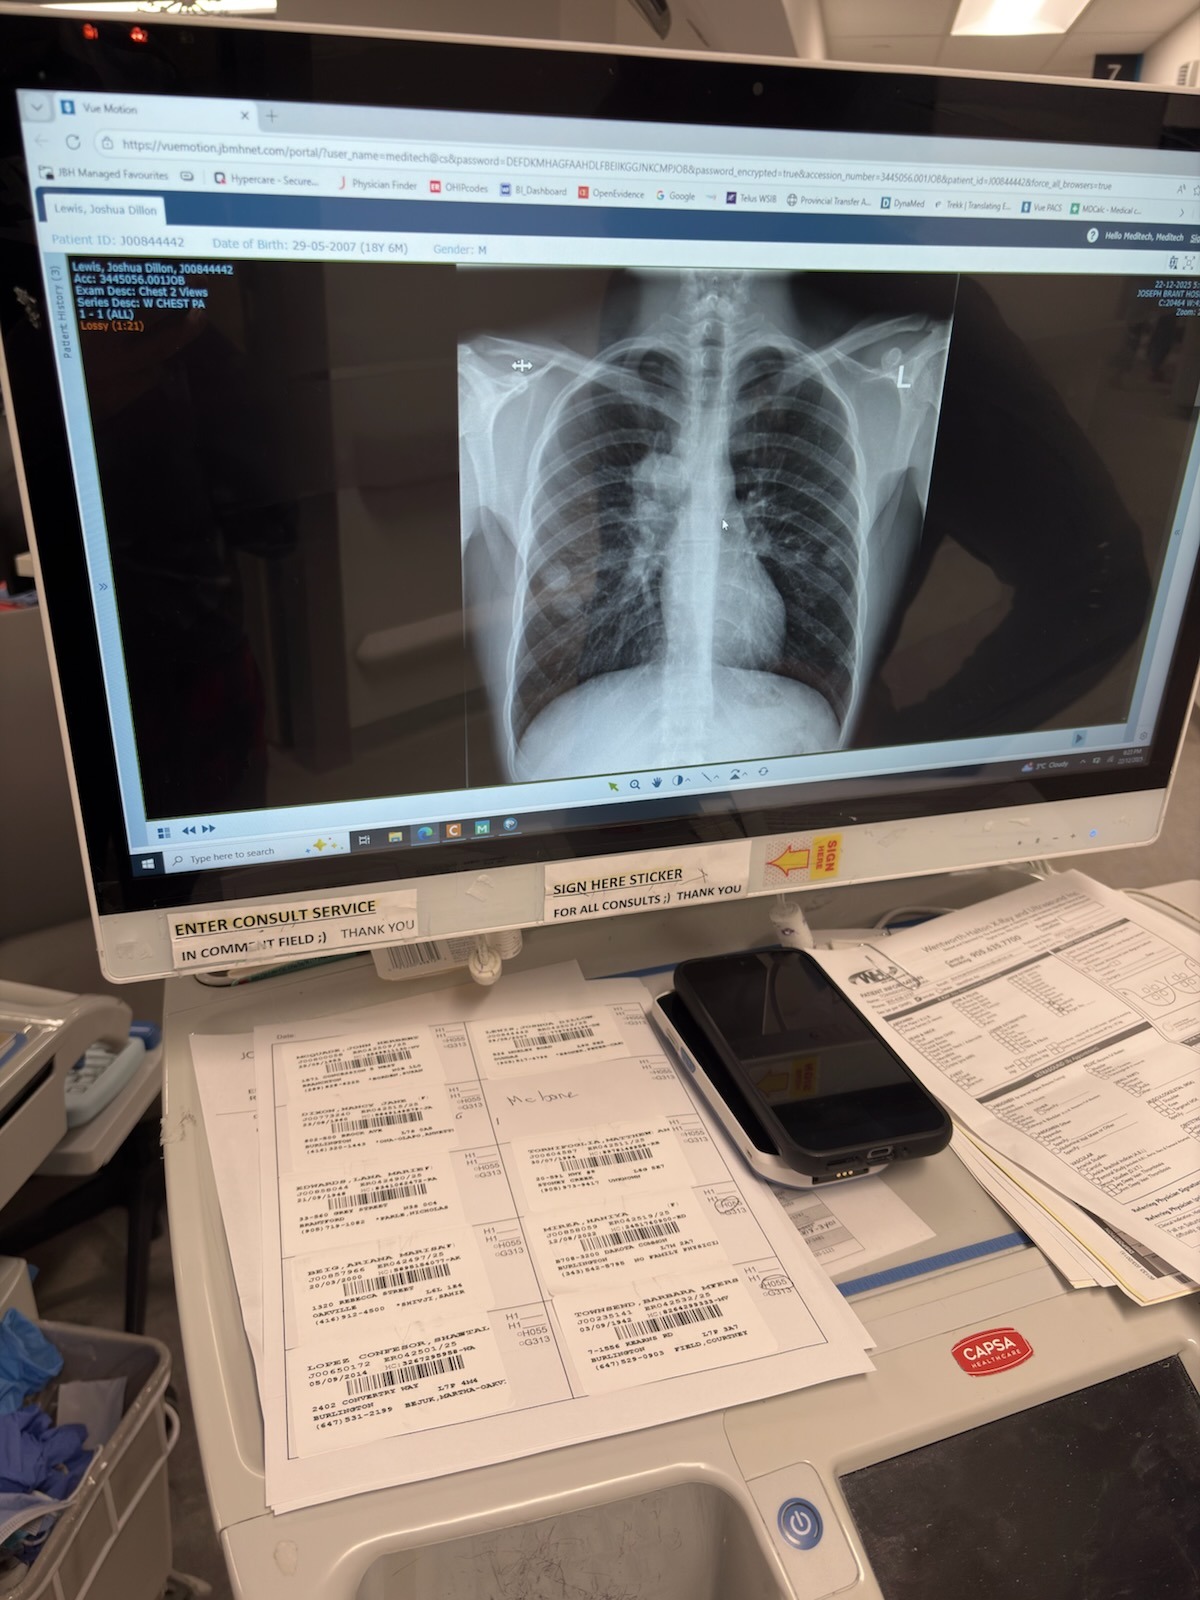

Last year Joshua was diagnosed with testicular cancer ..just after his 18th birthday... he had surgery to remove the cancer... and still pushed through and graduated high-school with honors.. things were going well .. he got his first apartment.. he was working and his health was improving . However a few months later things took an awful turn and his cancer spread and he has been diagnosed with stage 4 lung cancer and currently going through heavy chemo treatments weekly.